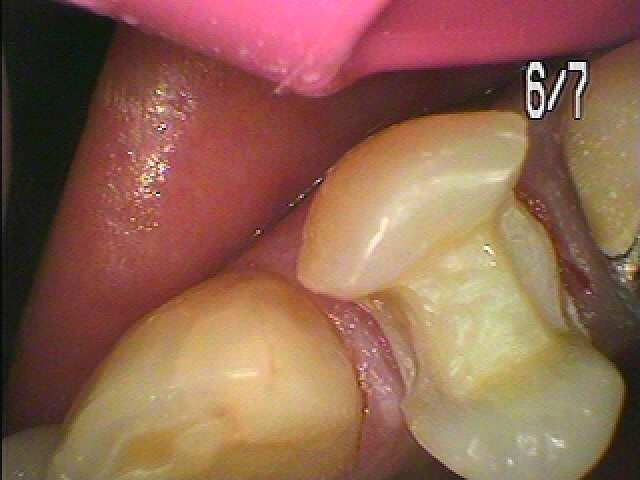

セレックセラミックにて審美的に綺麗に修復しています

汚れも付きにくく現代病であるアレルギーも無く良いマテリアルになります

本来の歯のようにきれいに仕上がりました